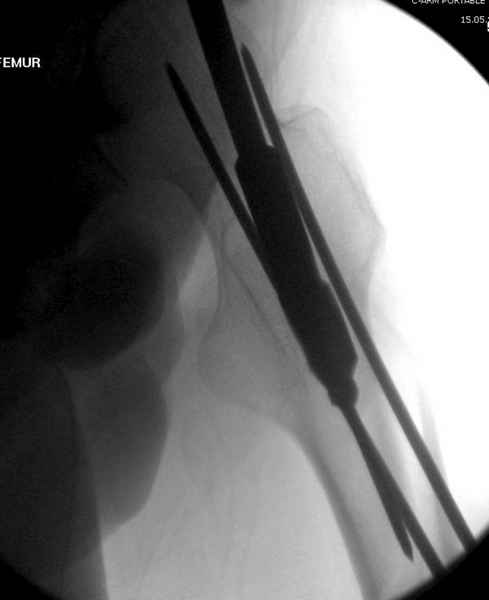

Для профилактики дальнейшего раскола в шейке предварительно во время проксимального рассверливания спереди и сзади провели временные спицы, которые в дальнейшем были заменены на шурупы (miss nail method)